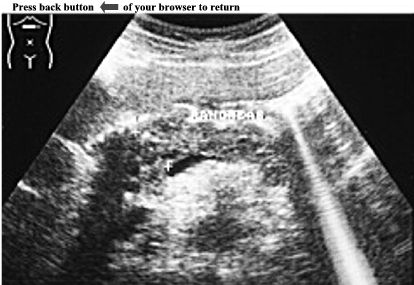

CASE

5:

Ultrasound

examination

of

an

asymptomatic

adult

patient.

Left

kidney

is

enlarged

and

shows

numerous

anechoic

areas

in

the

cortex

medulla.

These

vary

size

their

margins

are

irregular.

largest

one

measures

3.3cm

X

1.6cm.

Further

reveals

right

as

well.